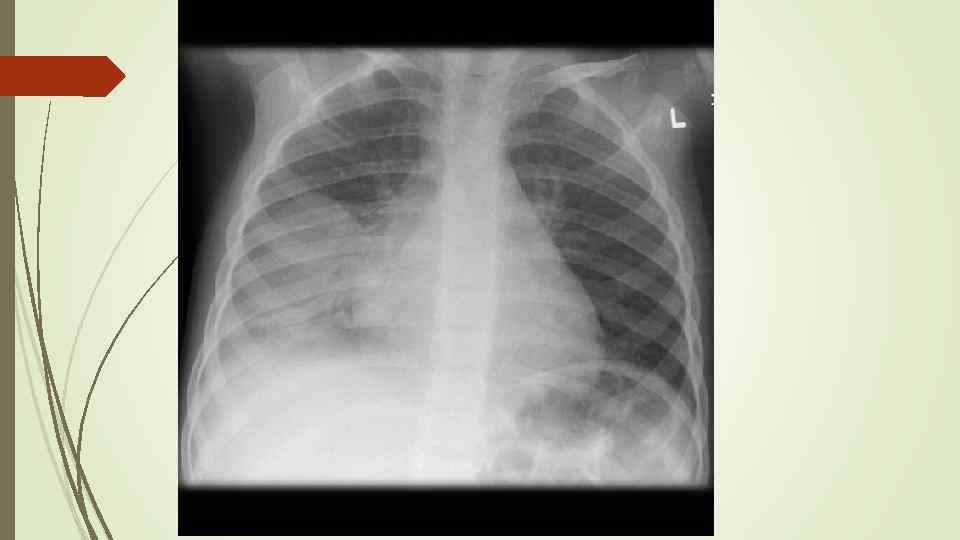

Бронхопневмония Характерно наличие двухсторонних множественных очаговых теней. Контуры очагов нечеткие, интенсивность тени небольшая. Инфильтрация неоднородна. Мелкие, малоинтенсивные очаги не всегда выявляются на снимках. Легочный рисунок усилен на всем протяжении легких. Корни расширены, не структурны. Как правило, отмечается реакция плевры, могут быть и экссудативные плевриты.

Бронхопневмония Характерно наличие двухсторонних множественных очаговых теней. Контуры очагов нечеткие, интенсивность тени небольшая. Инфильтрация неоднородна. Мелкие, малоинтенсивные очаги не всегда выявляются на снимках. Легочный рисунок усилен на всем протяжении легких. Корни расширены, не структурны. Как правило, отмечается реакция плевры, могут быть и экссудативные плевриты.

bronhopneumoni

bronhopneumoni